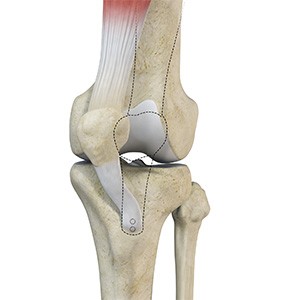

Patellofemoral Stabilisation

Patellofemoral stabilisation is a broad term that refers to surgeries employed for stabilisation (prevention of dislocation) of the patella for the treatment of patellofemoral instability.

Patellofemoral Realignment

Patellofemoral realignment is a surgical procedure performed to treat symptomatic patellofemoral instability that does not respond to nonsurgical treatment measures.